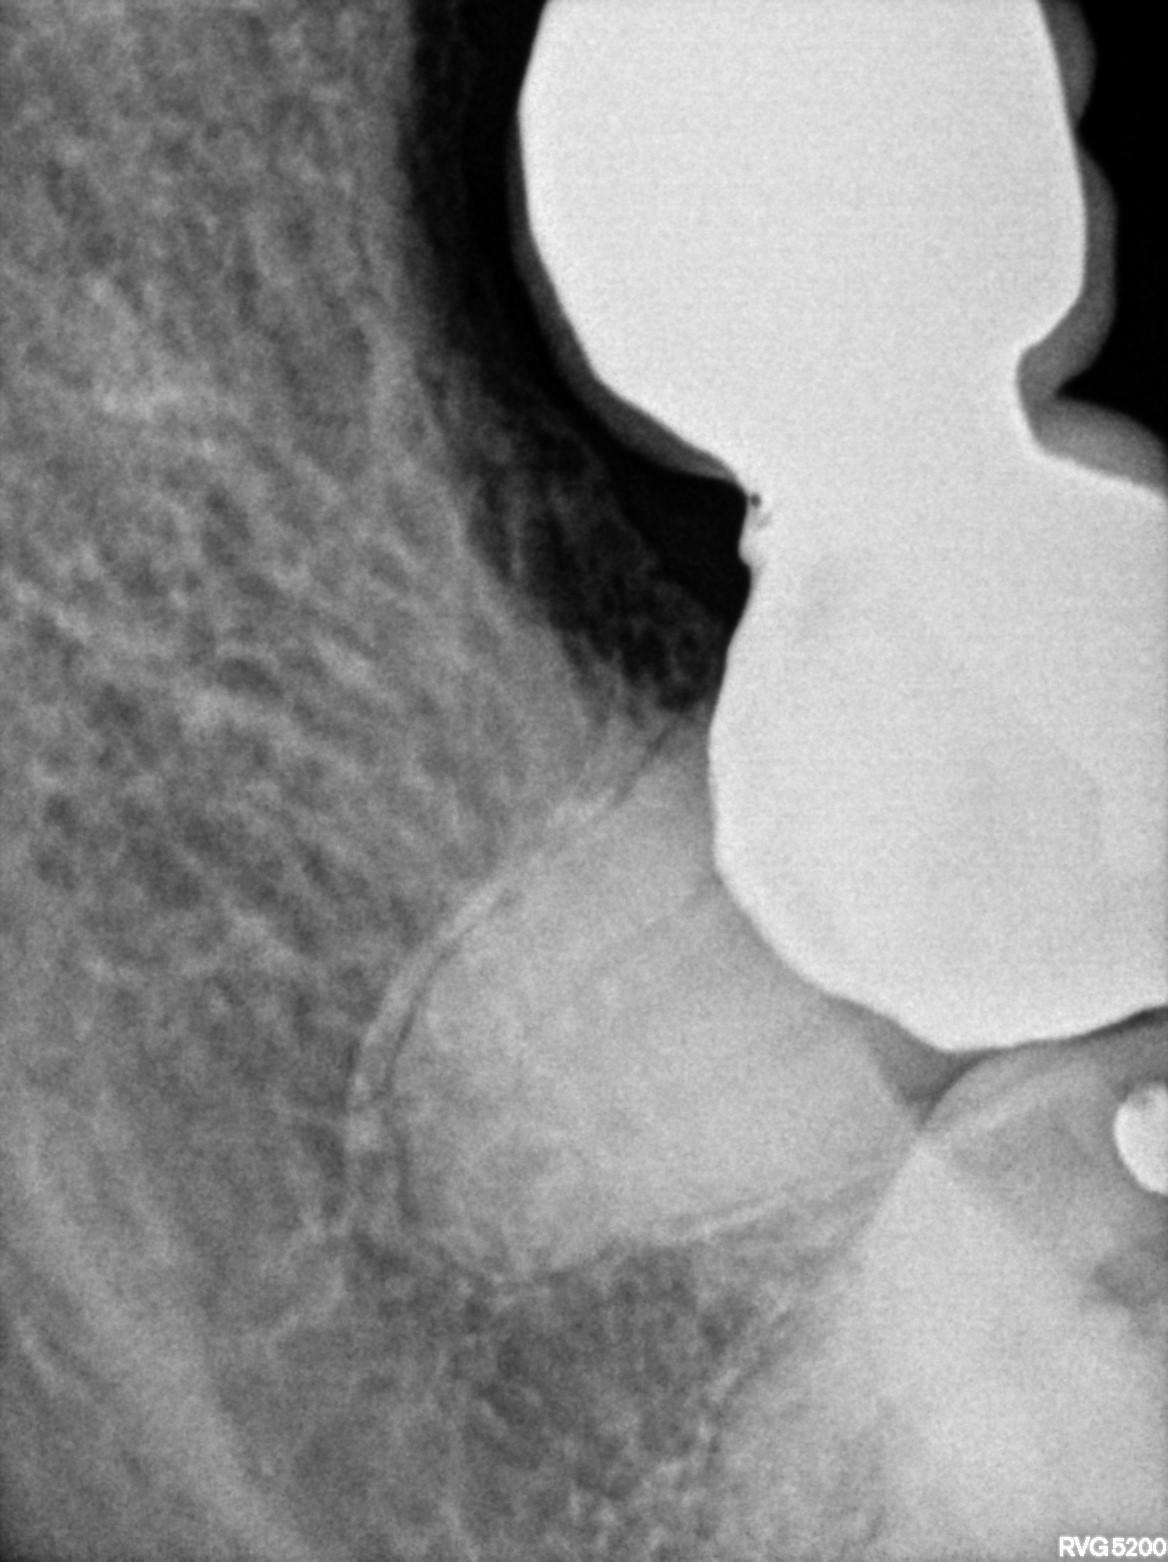

Dental Radiographs FHIR: DocumentReference · LOINC 24641-7

xray_1765005927_0.jpg

24641-7